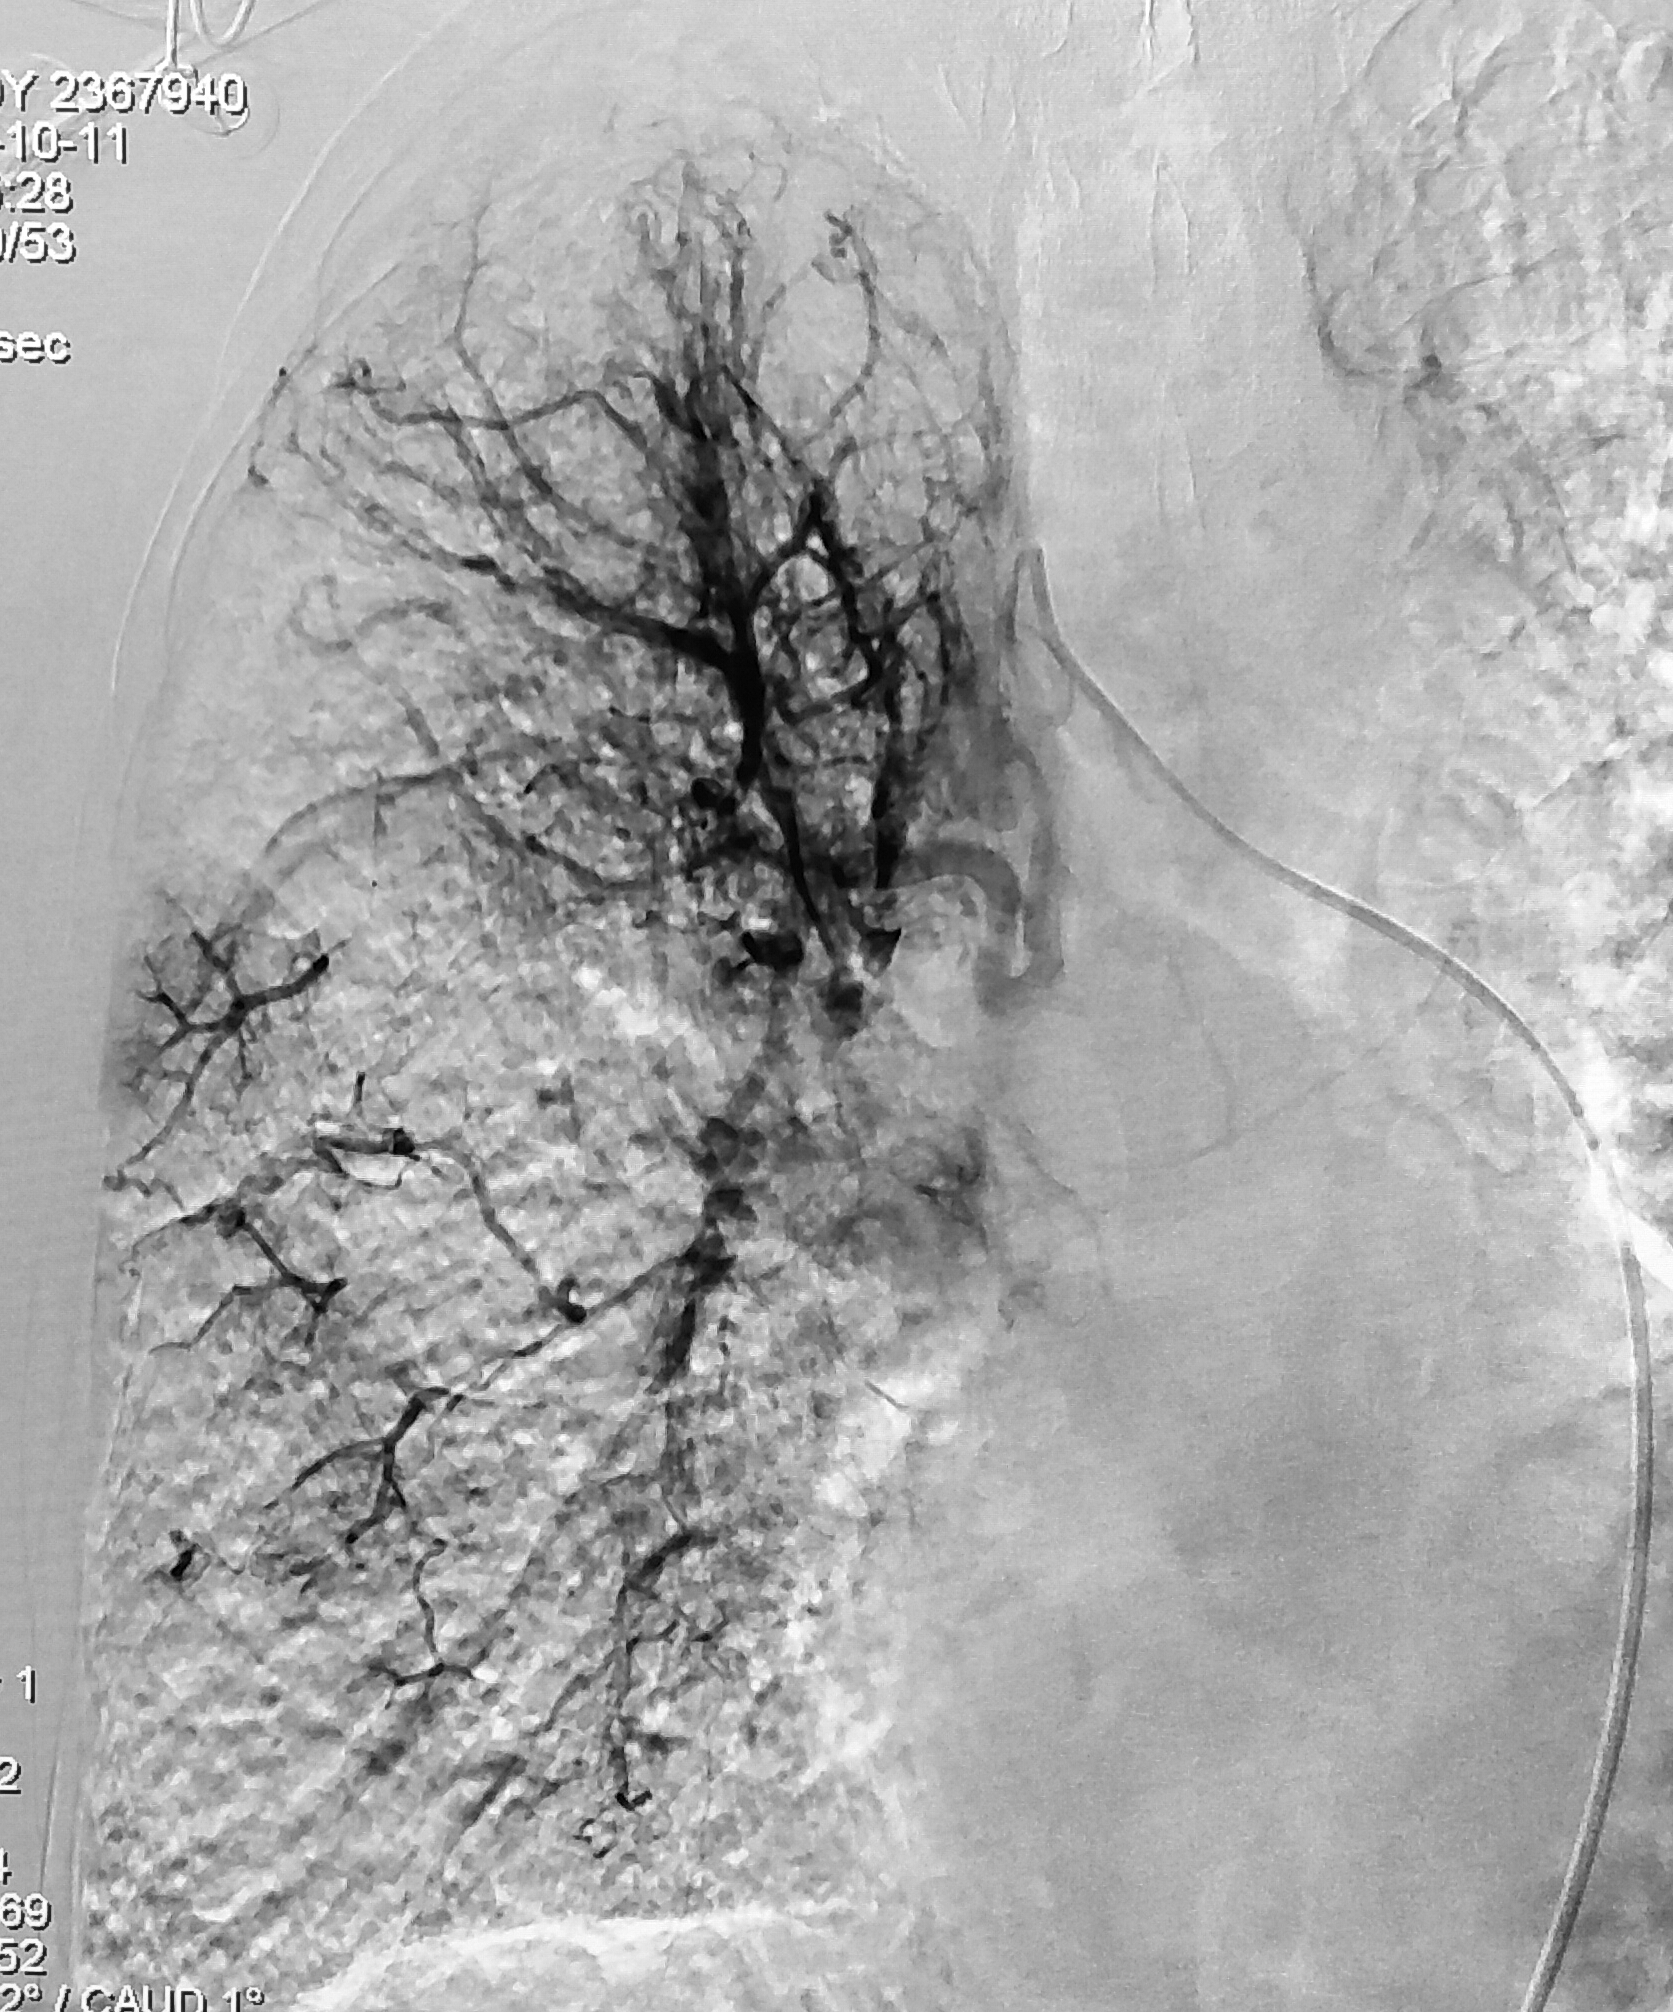

我用一根细小的穿刺针,从患者的右腿根部穿刺动脉,顺利地插管到主动脉造影,看到患者的右侧支气管动脉明显增粗,杂乱不堪,还有对比剂外溢现象——出血的责任血管找到了!

右侧支气管动脉造影图像

于是,再将导管进一步插到右支气管动脉内,证实无误后,对这条责任血管进行了栓塞——直接堵住出血的血管。很快就完成了操作,栓塞完成后造影复查可见出血的血管不再显影,这是很直观的影像学评价手段。随后,患者的咳血症状很快就停止了,患者的呼吸、心率、血压也逐渐恢复了正常,临床评估也证实有效。